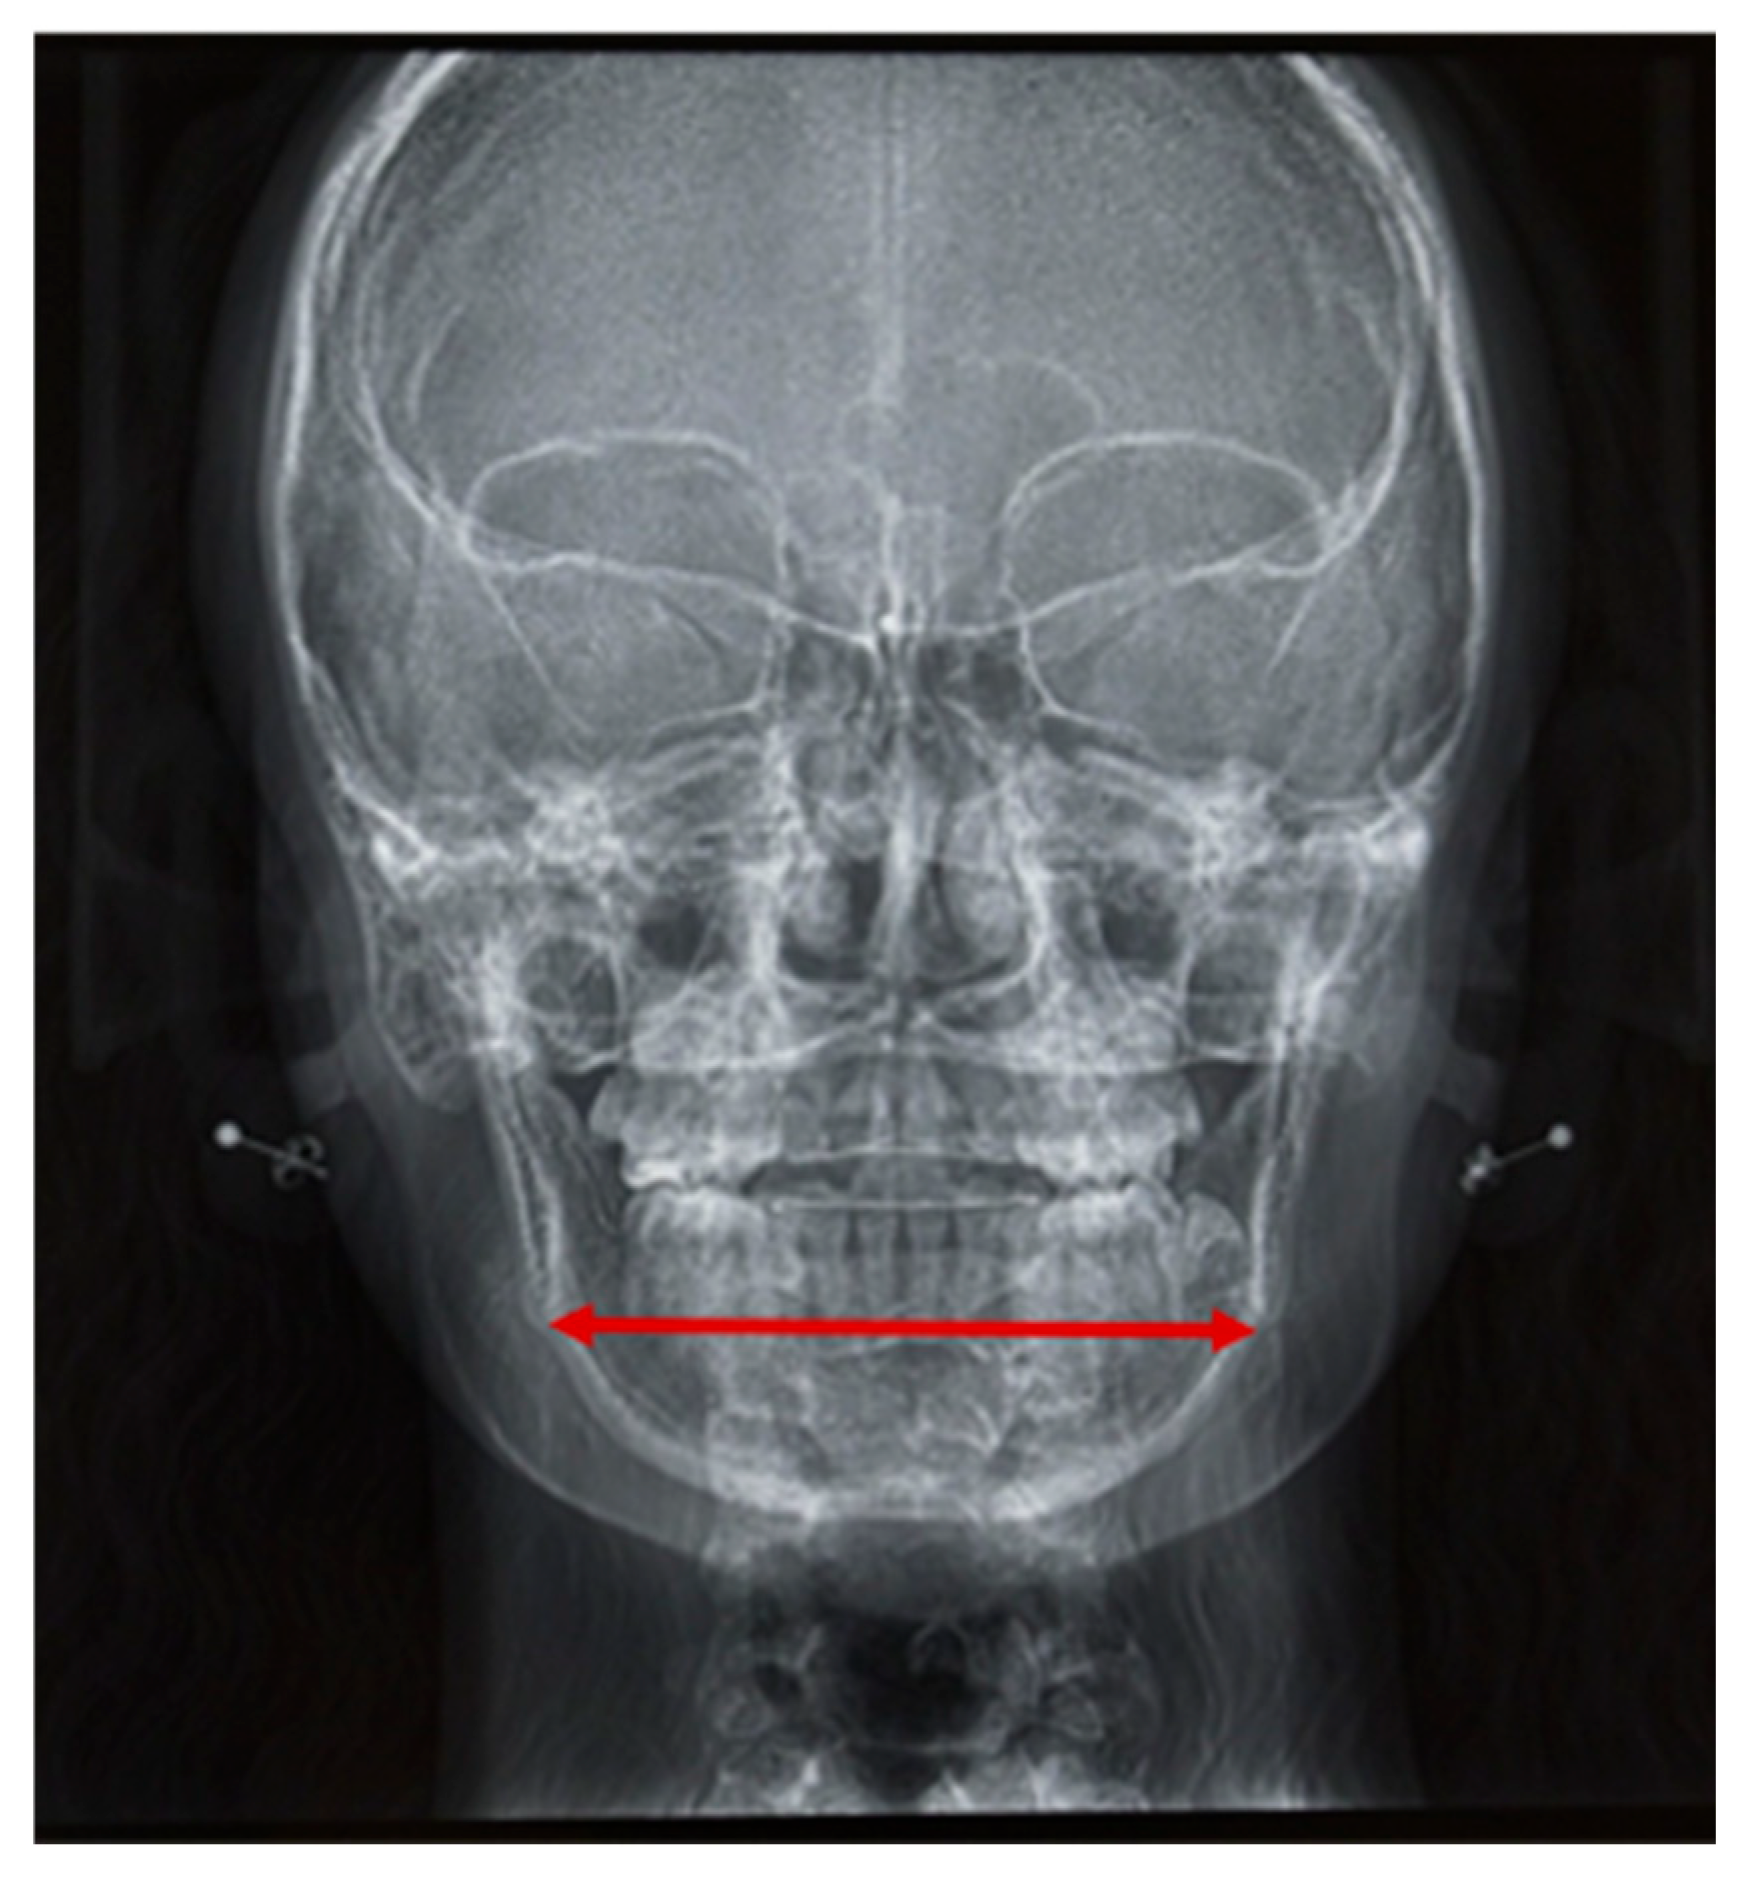

Mandibular width was determined by measuring the distance between the two antegonial notches on frontal cephalometric radiographs. Age-dependent reference values were used for this analysis (analysis according to Ricketts [38]) (Figure 5).

Mandibular width was inferior to the norm in half of our patient group (n = 14). However, the median difference between the measured values and the age-specific norms (according to Ricketts [38]) was −2.0 mm. Thus, patients showed a tendency toward a decreased distance between the two antegonial notches, although it was not significant (p = 0.821). Two patients with Sticker syndrome were included in this group. The differences between their determined values and the age-specific reference values were below the median for the entire patient group (−5.6 mm and −3.25 mm, respectively). Their mandibles were narrower than those of iRS patients.